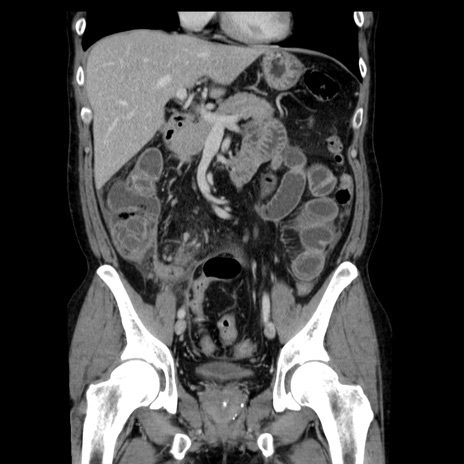

症例29(冠状断像)

【症例】40歳代男性

【現病歴】2日前から胃痛あり。徐々に周期的な激痛に変化した。本日になっても激痛があるため受診。

【身体所見】意識清明、BT 38-39℃台あり、腹部:膨満、やや硬、右下腹部に圧痛あり。

【データ】WBC 8500、CRP 23.26